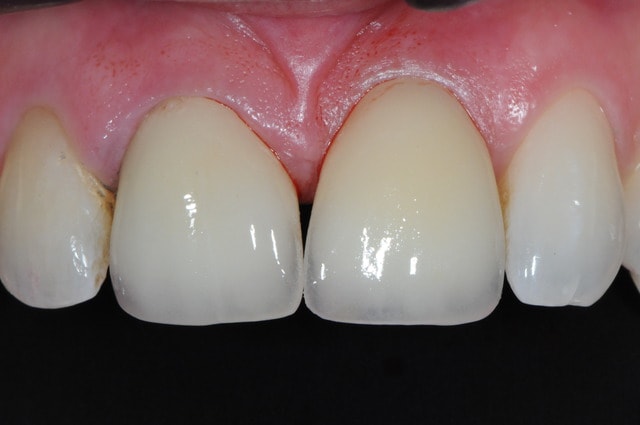

les couronne ont été posées hier justement!

suis pas trop satisfait du résultat car le patient voulait fermer les espaces inter incisifs et cela donne un aspect "pelle à tarte"

comme promis...

il faudra attendre un peu pour voir ce que ça donnera pour la gencive dans quelques mois. dommage que le patient ne voulait pas de conjonctif enfouie pour épaissir sa gencive.

Joli

Tu as un radio finale ?